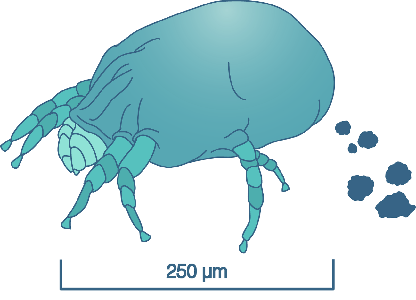

Detailreiche Fotografien aus der medizinischen Praxis ergänzen die Texte; moderne, genaue,

wissenschaftliche Zeichnungen geben Einblick in die Anatomie und die Funktion der Lunge und

anderer Organe.